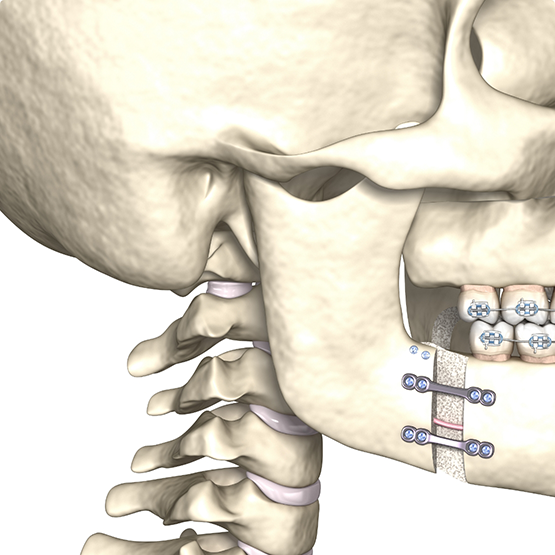

Your surgical treatment is coordinated between the orthodontist and the oral surgeon. The orthodontist will start your orthodontic treatment with braces or aligners and will prepare the patient for the surgery by the surgeon (pre-surgical orthodontic treatment phase). During the pre-surgical orthodontic treatment phase, the orthodontist will typically reduce the dental compensation in the patient’s dentition, which usually results in worsening the patient’s malocclusion (bite). Once the surgery has been performed by the oral surgeon, the orthodontist will finish the orthodontic treatment (post-surgical orthodontic treatment phase). With new advances in surgical techniques, the post-surgical recovery time has been significantly reduced, and patients can return to normal activity in a short time (7-14 days).

Surgical Case

Patient presented with a class III profile, underbite. The patient underwent orthodontic and surgical treatment. Facial profile showed significant improvement.